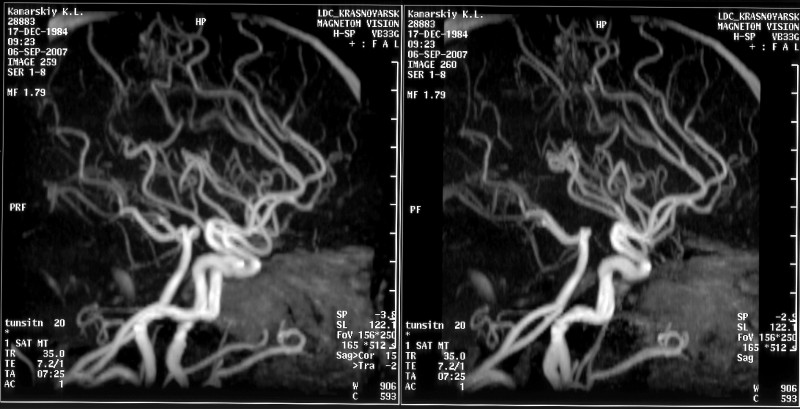

Здравствуйте, Артерио-Венозная мальформация 1,6*1,6*2,7 в правой теменной области.  Гамма Нож или эмболизация? : Насколько болезненны , сколько длится операция по времени? Какой метод безопасней, Какие осложнеия возможны, Реабилитация сколько занимает времени?